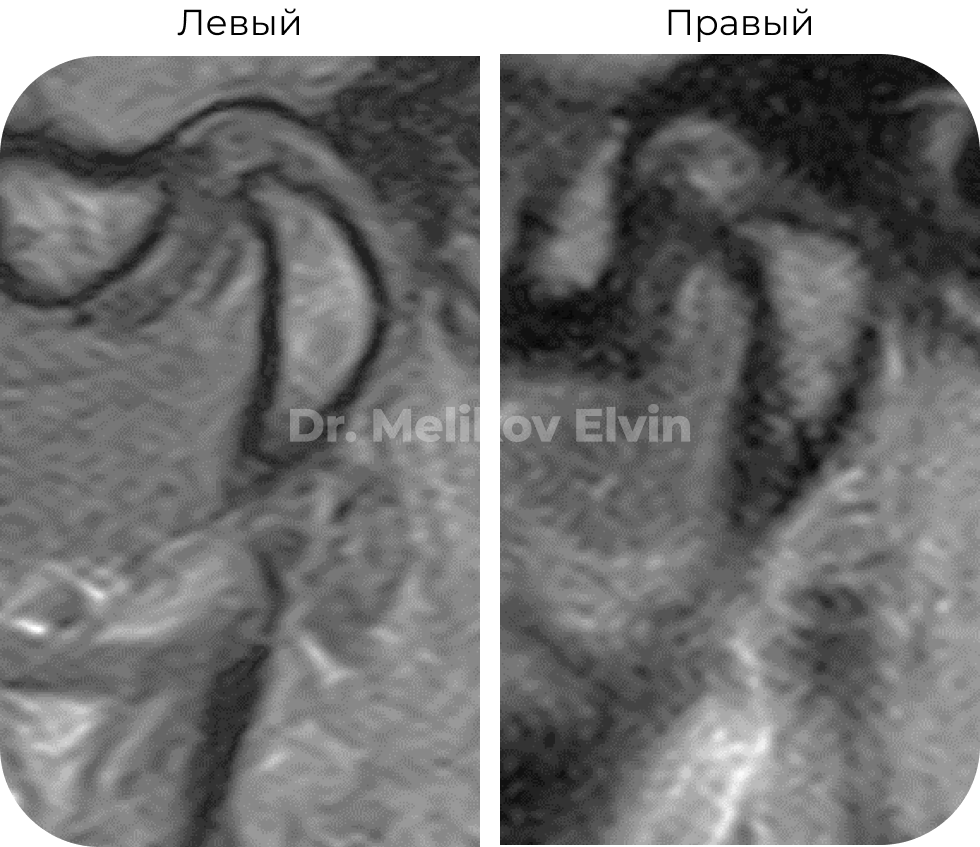

Магнитно-резонансная томография ДО лечения. Заключение

МР-картина может соответствовать дисфункции обоих височно-нижнечелюстных суставов: невправляемого вывиха суставного диска справа /с умеренной дегенерацией ткани диска/, вправляемого подвывиха суставного диска слева. Остеоартроз обоих височнонижнечелюстных суставов 2 ст. / вероятно на фоне нерезких диспластических процессов/. МР-картина минимальной гипермобильности левого ВНЧС.

В сравнении с предыдущим исследованием отмечается отрицательная динамика.